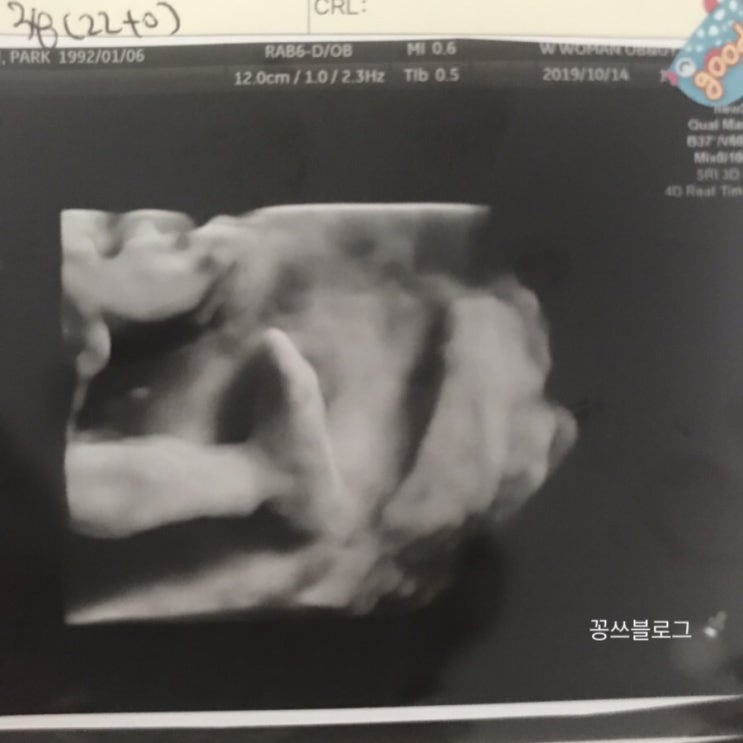

12# 임당검사,조리원예약,입체초음파 / 임신25주 26주

11# 쑥쑥 두루 /임신 23주 24주

@23주 6일 남편 첫 태동 느낀날 두루는 아직 손에 태동 느낄만큼 크게 움직이는 경우가 드물어서 꿈틀한다 ...

10# 정밀초음파 /임신 21주 22주

@배가 꿀렁하는게 보일정도로 태동을 한다 손만올리면 멈춰서 손에선 태동 못느꼈는데 21주6일 손으로 태동...